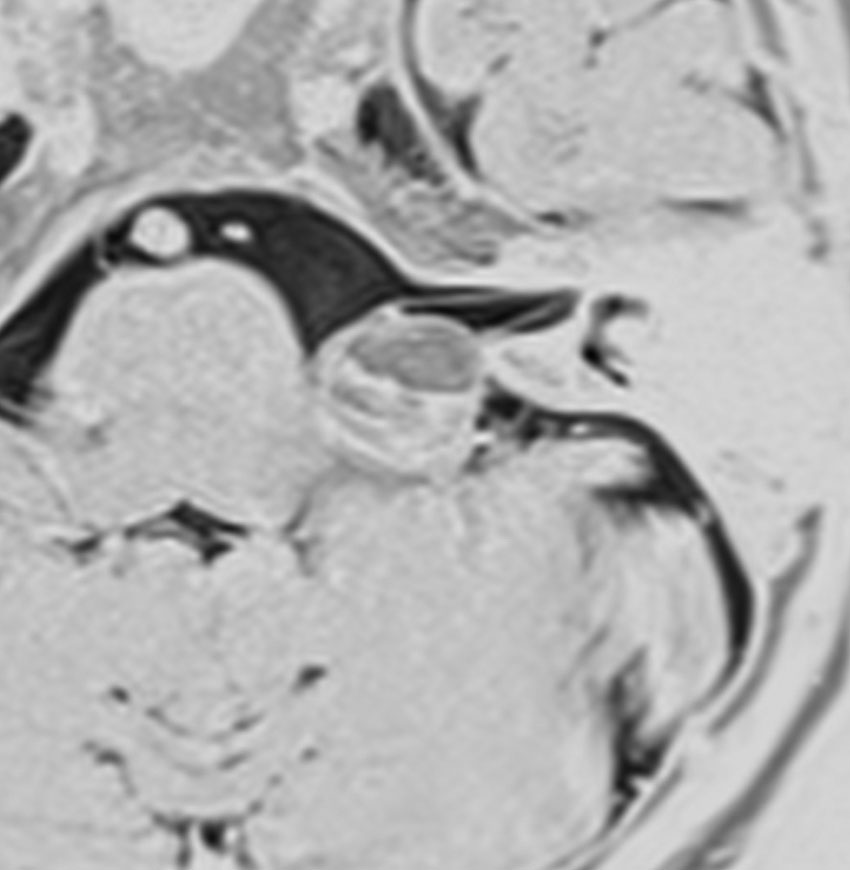

左上のT2*でみられるように多発性海綿状血管腫の成人男性に発生した中脳海綿状血管腫です。複視と歩行失調で発症して,数回の脳幹部出血を繰り返し,水頭症になったために第3脳室開窓術がなされました。それでも出血は止まらず、両側の動眼神経麻痺による両側眼瞼下垂,歩行失調,嚥下障害などさまざまな中脳症状が進行しました。

しかたがないので手術で摘出しました。なんとか眼瞼が持ち上がるようになり歩行も可能で嚥下もできます。幸いだったのは感覚路(脊髄視床路)の障害による体性疼痛が生じなかったことです。

手術は経テント法 OTA という手法でした(クリックと手技が書いてあります)

片方の下丘の損傷だけでは神経脱落症状が出ないので,中脳内部の腫瘍を摘出するには下丘という狭い場所を切開して入りますが,この患者さんは左上丘も出血のために破壊されていて,間口が広かったといえます。でもこの手術は難しすぎるので決して積極的にはしません。